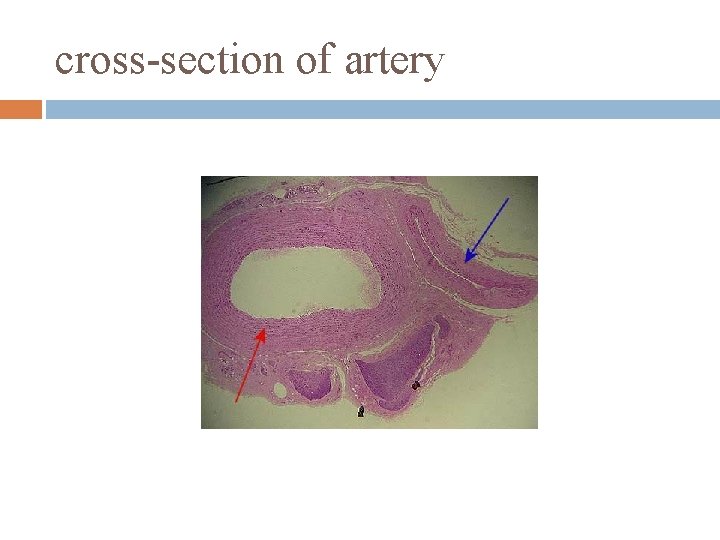

cross-section of artery